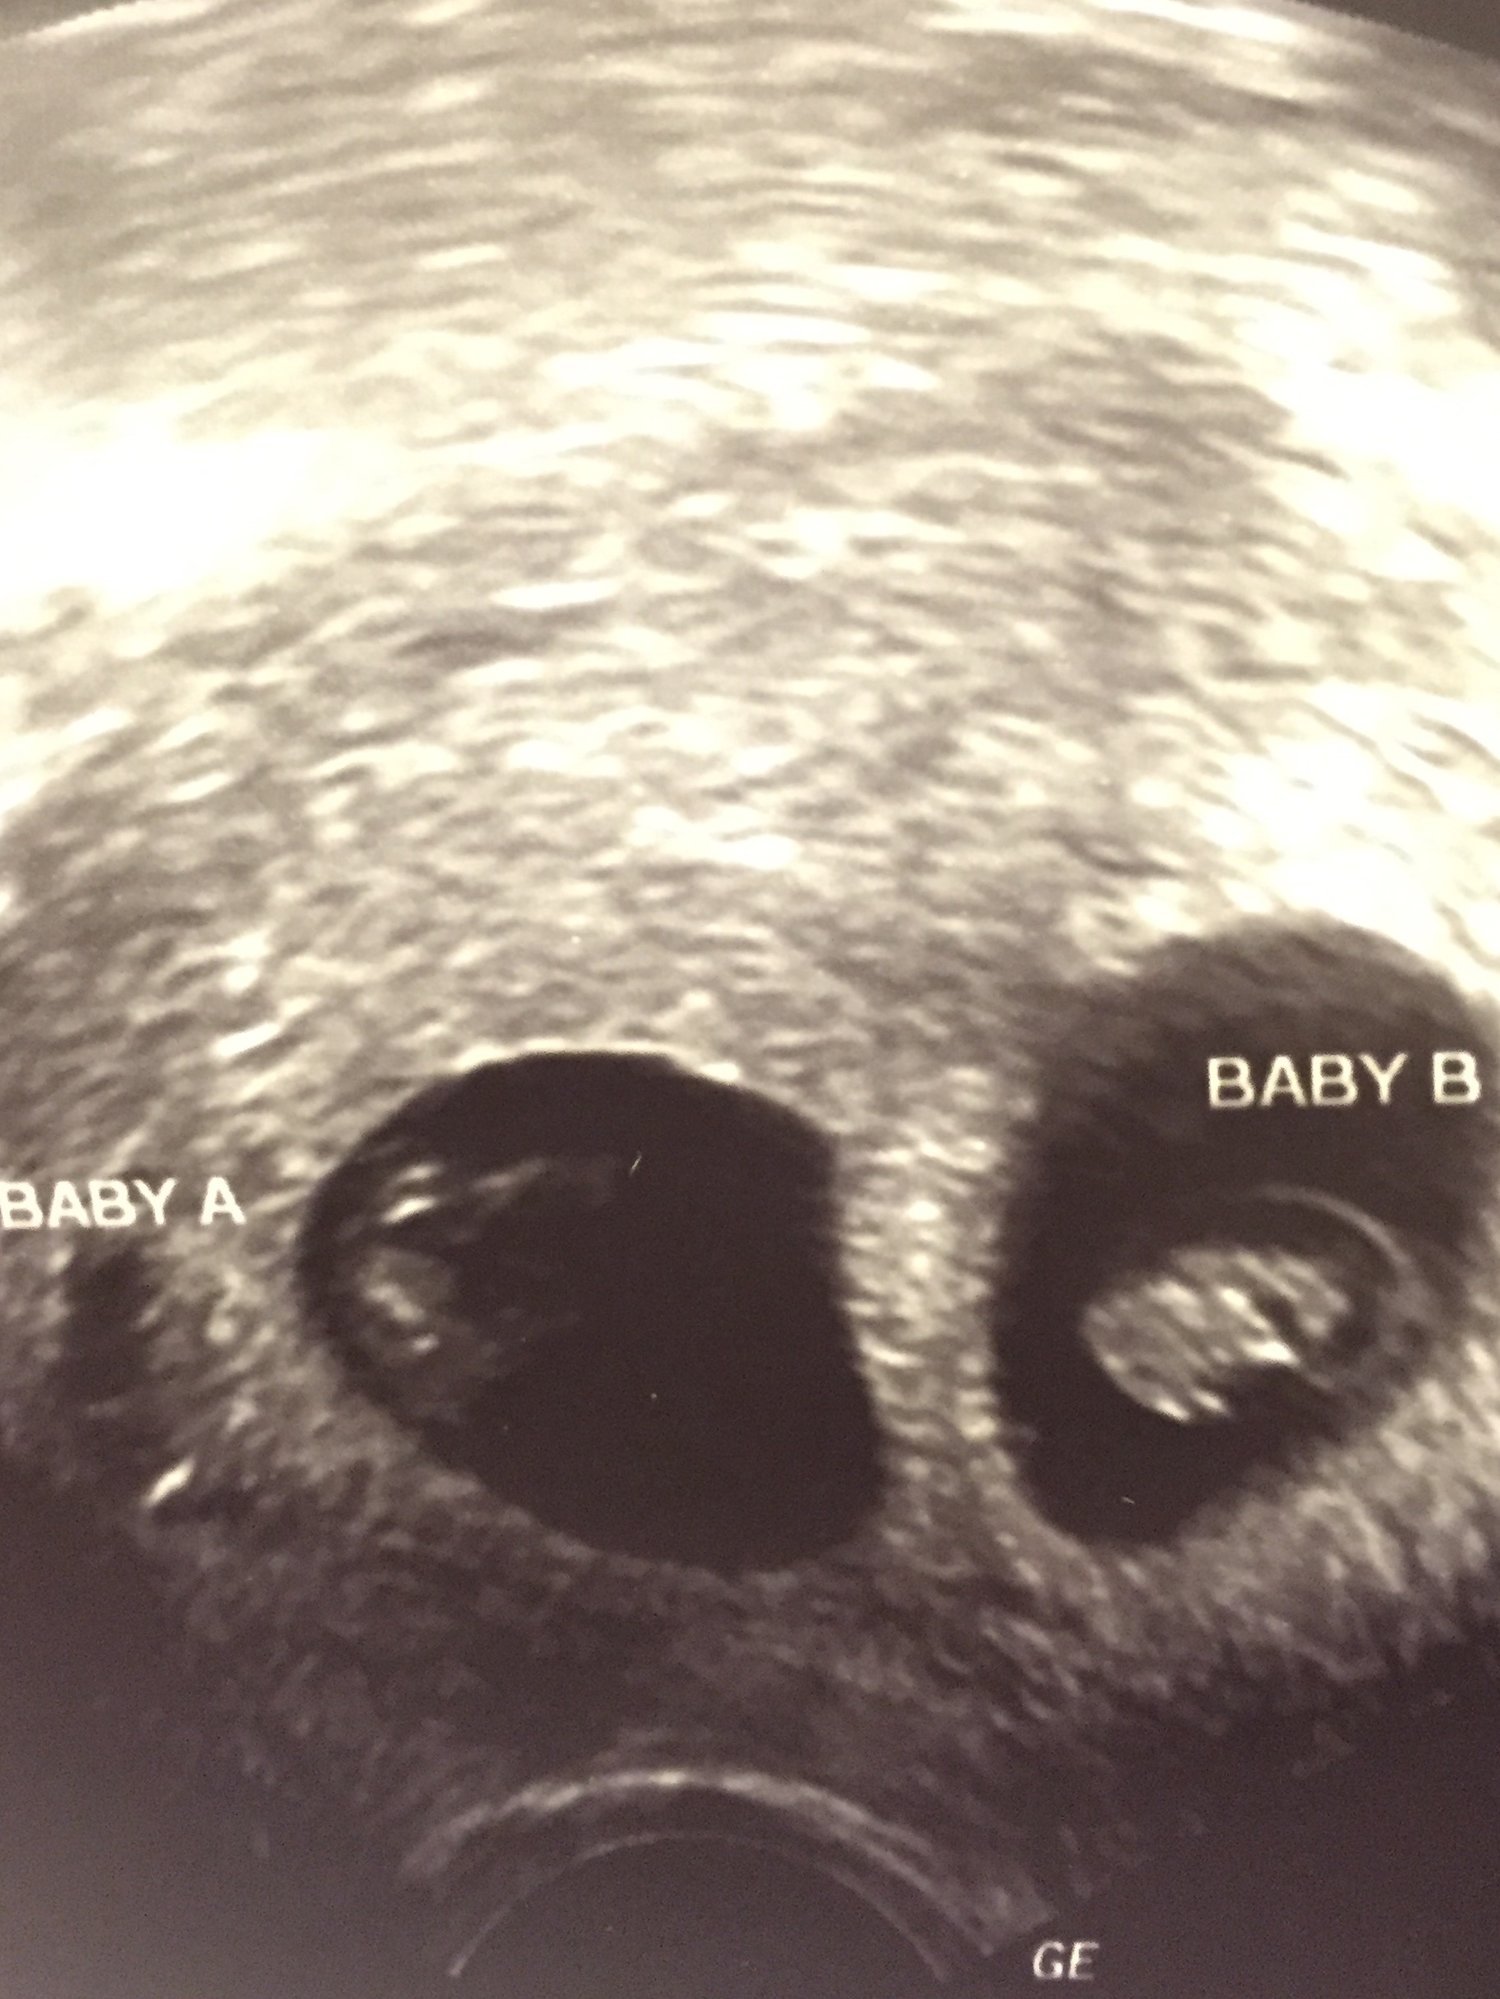

At this point it's almost an anomaly to have a singleton on this board.